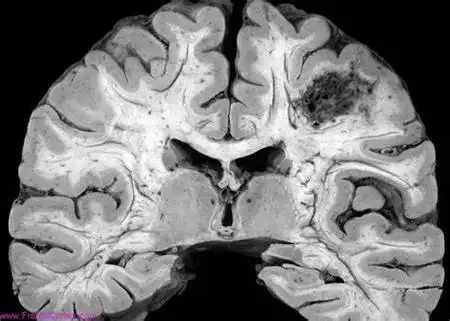

术战癫峰第57期左侧巨脑回畸形行大脑半球离断术一例

巨脑回1

行过程中受阻,导致脑组织不同程度的发育畸形,包括无脑回-巨脑回畸形

颅脑先天性疾病影像诊断